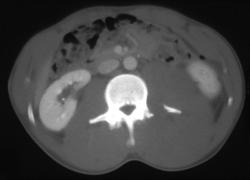

Transverse Process Fracture With Hematoma